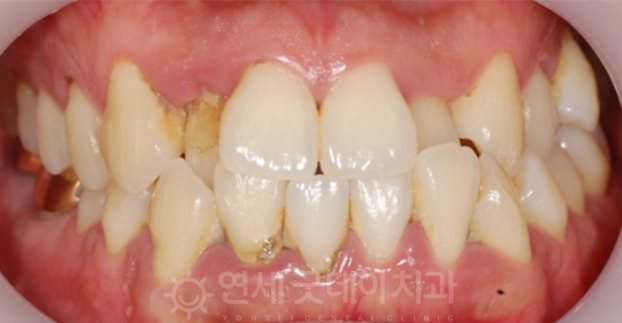

CASE 1 – 치근피개술

치근피개술 치료 전(좌) 치료 후(우)

잘못된 양치질이나 구강관리 또는 이악물기 같은

습관이 반복되면서 위 사진과 같이

잇몸퇴축현상이 일어날 수 있습니다.

대부분 이시림 현상을 겪게 되고,

심미적인 문제로 인해 병원을 찾게 되는데요.

이렇게 잇몸소실로 인해 치아뿌리가 드러난 경우

치근피개술로 개선을 해드리고 있습니다.

이는 입천장 부위의 점막 일부분(구개상피 또는

결합조직)을 채취하여 노출된 치아 뿌리에 덮어

이상적인 잇몸형태로 회복할 수 있답니다.